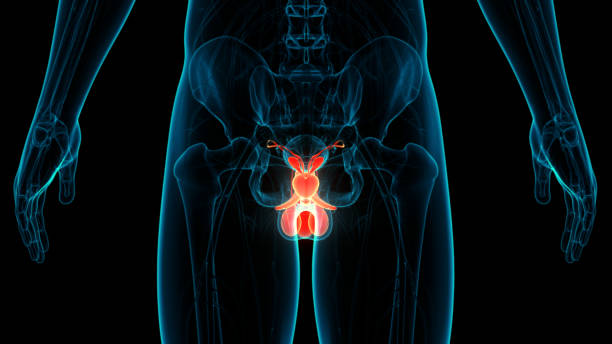

전립선비대증은 남성에서 주로 발생하는 전립선의 비대증입니다. 전립선은 남성의 생식기로서, 요도 주변에 위치하며, 요도를 통해 배뇨와 정액의 배출을 조절합니다. 전립선비대증은 나이가 들수록 발생 확률이 높아지며, 대부분의 남성이 한 번 이상 경험하게 되는 질환입니다.

전립선비대증은 전립선의 세포가 비정상적으로 증식하면서 발생합니다. 이러한 세포 증식으로 인해 전립선이 커지면서 요도 주변을 압박하고, 배뇨와 관련된 증상을 유발합니다. 전립선비대증은 일반적으로 배뇨 불편, 방광염, 자주 병원가는 등의 증상을 유발합니다.

전립선비대증의 정확한 원인은 알려지지 않았으나, 나이와 성호르몬의 변화, 유전적 요인 등이 영향을 미친다는 것이 알려져 있습니다. 진단은 일반적으로 증상 및 신체검사와 방광내시경, 요로피부종영상술(IVP), 전립선 생검 등의 검사를 통해 이루어집니다.